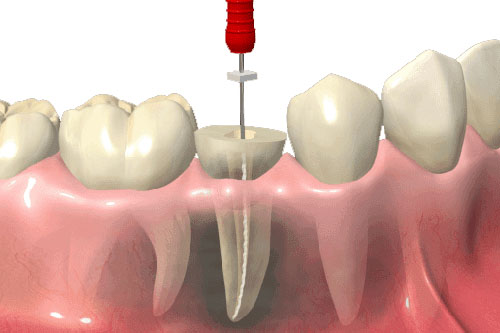

¿Cómo se realiza un tratamiento de conducto?

El tratamiento de conducto se realiza mediante la limpieza y desinfección del interior del diente afectado, seguido de la obturación con un material especializado para sellar el conducto y prevenir infecciones futuras.